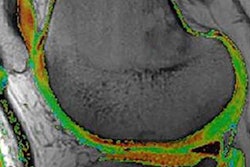

After removing data outliers and smoothing the contours, the joint space is output from CT as the 3D object in yellow, with the green (femur) and blue (acetabulum) regions representing the inner limit of subchondral bone for these structures. The MRI algorithm delivers combined cartilage thickness, but is being developed further to more accurately segment the individual femoral (purple) and acetabular (red) cartilage surfaces more accurately.

3D object output from joint space mapping."In joint space mapping results, we see we can define ... two cartilage surfaces, and importantly what we have here now are volumes of interest in which we can perform other types of sampling," Turmezei said.